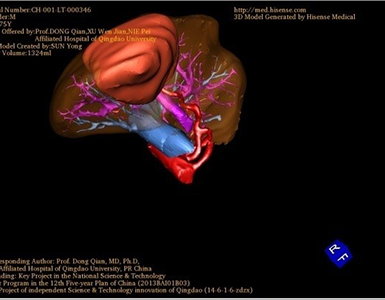

胆管细胞癌-CH-001-LT-000346

一般情况:CH-001-LT-000346,74岁男性患者。

将0.625mm双源薄层CT资料的静脉期和动脉期Dicom格式文件导入海信CAS系统。

通过调节窗宽窗位调整CT序号,对肿瘤,肝实质,胆囊,下腔静脉,肿瘤,肝动脉、门静脉及肝静脉等进行三维重建;系统自动计算肿瘤体积和肝脏体积。(图2—截图1---后链接截图2)

模拟手术操作,自动计算切除肿瘤体积。肝脏体积为1324ml,肿瘤体积为286.1ml,肿瘤体积为肝脏体积的21.6%,通过比对70-80岁正常肝脏体积为1118.08±190.14ml,通过术前模拟手术,精准判断切除后剩余肝脏体积能耐受,避免肝衰竭发生。术前手术方案的规划。

麻醉成功后,病人平卧位,常规碘伏消毒手术区皮肤,铺无菌巾、单。取右肋缘下切口,分层入腹,纱布垫护皮,上框架拉钩。探查见:腹腔粘连严重,肝脏质地及形态可,右肝Ⅴ、Ⅵ段交界处,可触及直径8cm不规则肿块。既往胰十二指肠切除术手术史,仔细分离腹腔粘连,游离右半肝,肿瘤未侵犯胆肠吻合口,决定保留吻合口,行姑息性肝癌肝部分切除术。游离肝脏与周围组织粘连,沿肿瘤边缘约1cm,依次钳夹、切断、结扎肝断面各结构,切除肿瘤及部分肝组织。断面渗血处分别缝扎止血,填塞止血敷料后,将创面对拢缝合。温蒸馏水3000ml冲洗腹腔,止血,于肝断面旁放置引流管1根于右侧腹壁穿孔引出。清点纱布器械无误,分层缝合腹壁切口。术中出血约500ml,未输血。术后血压120/65mmHg,术后病人安返病房。手术顺利,麻醉满意,解剖标本,肿块直径约8cm,灰白色,家属过目后送病理检查。结果回示:(肝右叶)低分化腺癌。手术时手术者可开启Hisense CAS系统手势控制功能,对肿瘤的解剖结构进行实时、全方观察、评估,起到术中导航作用。

术前三维重建:

重建图片